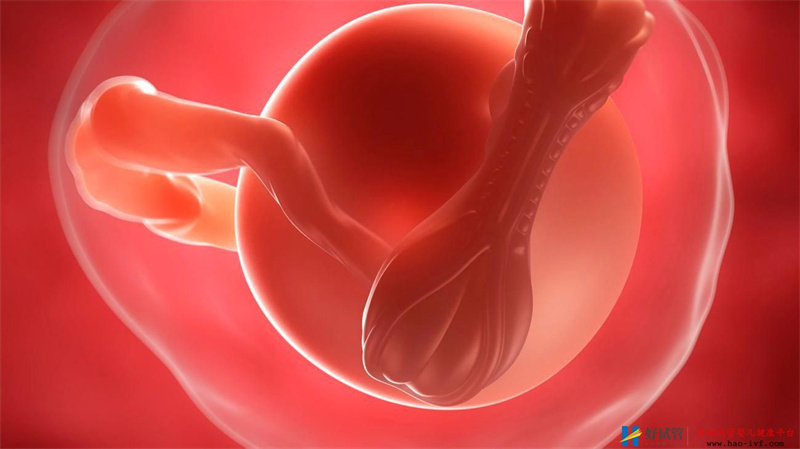

鲜胚是指取卵完后三天胚胎出结果,如果在这一天移植,就叫移植鲜胚,如果在这一天没有移植,而是把胚胎冻起来,以后再移植就叫做冻胚。 但是冻胚和鲜胚移植那个成功率更高一些呢?把胚胎冷冻起来会不会冻坏,或者胚胎活力降低,胚胎发育异常此类的问题发生?想必大家都有此疑问吧。 大多数人都感觉鲜胚更容易成功,因为它是刚取出的卵是新鲜的、更具有活力、更符合自然规律,想当然的就更容易成功;那么到底哪个成功率更高呢?

有临床表示鲜胚与冻胚成功率是一样的,也有研究表明冷冻胚胎移植成功率更高;其实从不同角度看,就有不一样的结果。 1.从胚胎的角度来说,鲜胚比较好,充满活力; 2.从母体来讲是冻胚好,但冻胚有可能造成胚胎质量下降; 另外补充一点,胚胎冷冻只是让细胞停止运动,并非中断,不会破坏胚胎的活力和规律,只要在给它恢复温度,就可以再生长。 前不久,冷冻了18年的胚胎被“唤醒”,并成功移植到妈妈的子宫内。经过十月怀胎,准妈妈顺利的产下一名女婴。这个女宝被称为中国最“抗冻”宝宝,她生产时重3300克,身体指标一切正常。 它的成功也成功的把胚胎冷冻技术带进了我们的视线,也因此宝妹才会谈冷冻胚胎这项技术。